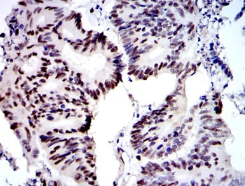

IHC    1/200 - 1/1000